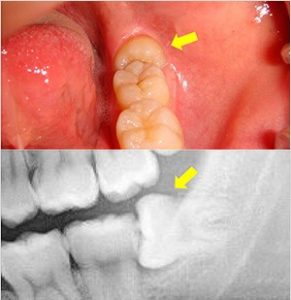

1.痛みや腫れがある

親知らずは歯列の中でも一番奥の歯であるため歯磨きが難しく、虫歯や歯周病になりやすいです。虫歯によって痛みが出る、もしくは歯周病菌が親知らずの周囲に感染することによって智歯周囲炎という病気を起こすことがあります。 これらの場合には痛みや腫れをともないます。 また智歯周囲炎は埋まっていない親知らずでも、上の歯との噛み合わせの刺激で起こる場合があります。